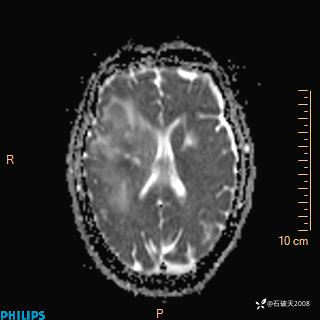

2024.2.21MR

增强冠状位